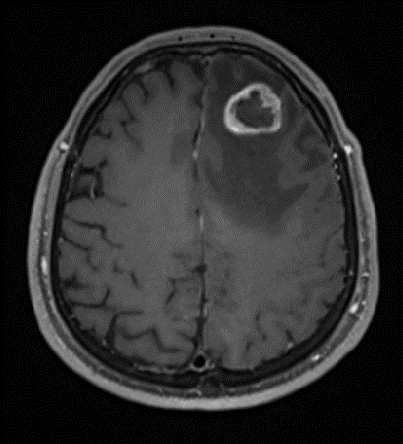

IRM post-opératoire d’une lésion tumorale frontale gauche

IRM pré et post opératoire d’une lésion tumorale frontale gauche